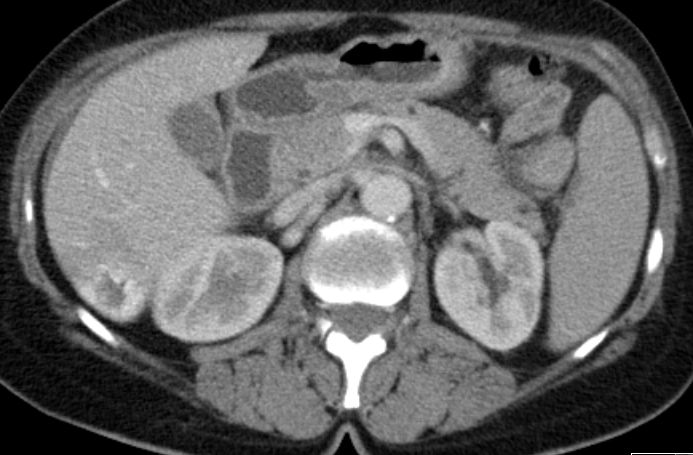

Magen 62-jährige Frau mit kolikartigen Flankenschmerzen durch einen mittlerer Harnleiterstein. Bei der Durchuntersuchung fand sich eine verdickte Magenwand. Endoskopisch chronische, nicht aktive Entzündung mit foveolärer Hyperplasie. Die Biopsie ergab Infiltrate eines gering differenzierten neuroendokrinen Karzinoms (G3, Ki 67 40%). Bekannte Haemangiome der Leber.